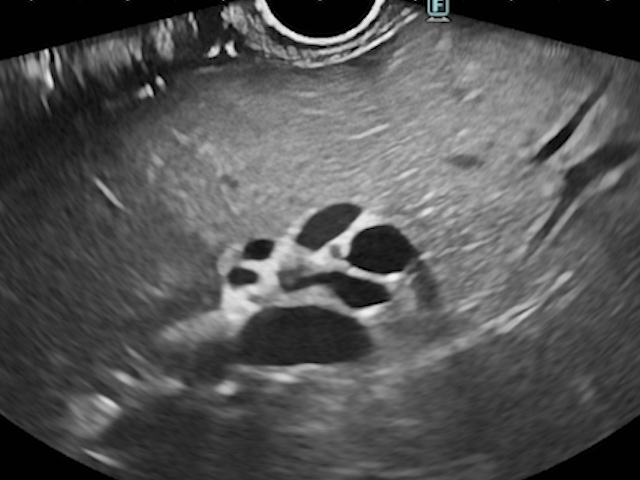

The cephalic pancreatic pseudocyst measured 83.5 mm, without solid components, and had a thin wall of 2.7 mm. Gastric station visualization was adequate, providing an optimal approach for EUS-guided cystogastrostomy (CGA-EUS) (Fig. 2).